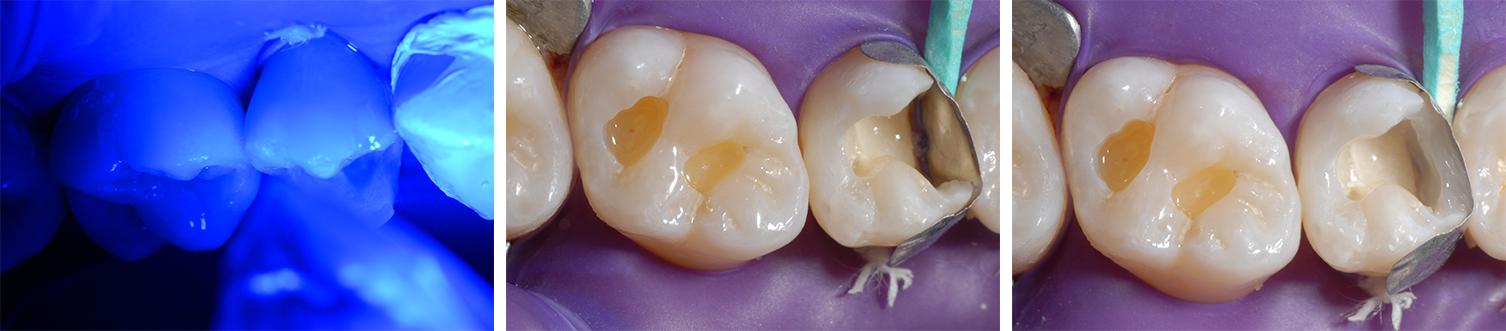

Après avoir mis le site entièrement à sec et éliminé complètement le tissu carieux au niveau de la dent 15, nous avons obtenu une cavité étendue et profonde à proximité de la pulpe, avec une couche de dentine résiduelle très mince au fond de la cavité (Ill. 2 et 3).

Ill. 3 : Dent 15 avec cavité préparée. On remarquera la profondeur et la proximité de la pulpe, ce qui représente une indication pour une protection pulpaire

Pour la procédure de traitement, nous avons opté pour une couverture indirecte de la pulpe avec un revêtement en hydroxyde de calcium du fond de la cavité, recouvert d’une couche de ciment verre ionomère IonoStar Molar de VOCO (Ill. 4 et 5). La dent 16 a également été préparée.

Nous avons commencé par obturer la dent 15. Le durcissement initial du verre ionomère a été suivi du conditionnement à l’acide phosphorique à 37% pendant 30 secondes sur l’émail, et pendant 15 secondes sur la dentine et au niveau du fond de cavité en verre ionomère (Ill. 6).

Ensuite, nous avons appliqué l’adhésif universel Futurabond U de VOCO, que nous avons ensuite polymérisé pendant 10 secondes (Ill. 7 et 8). À l’aide d’une matrice calée avec une clavette en bois, nous avons reconstitué la paroi proximale de la dent 15 avec une seule couche du matériau d’obturation nanohybride ORMOCER® Admira Fusion x-tra de VOCO, puis nous l’avons durcie pendant 20 secondes (Ill. 9 et 10).